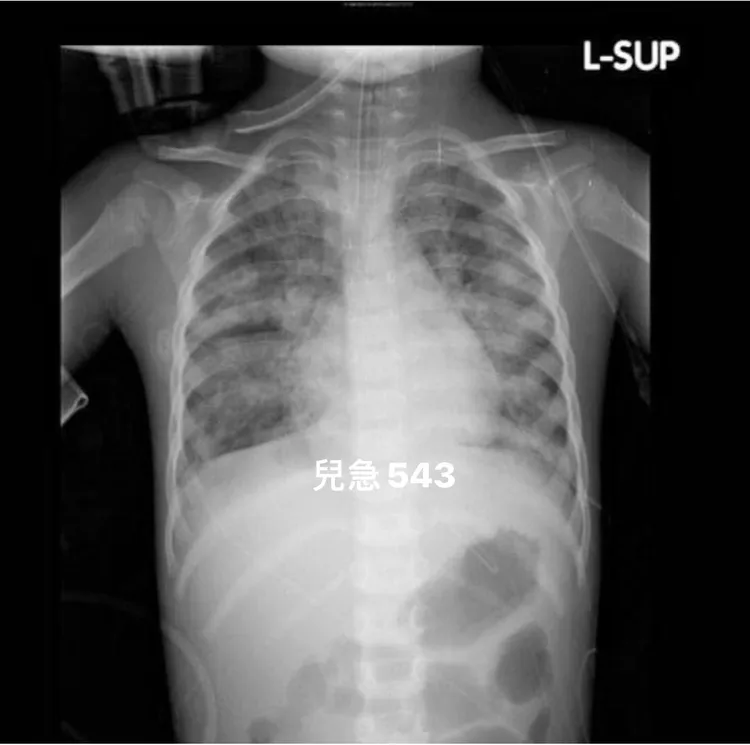

吳昌騰醫師分享幾年前,嚴重RSV感染的胸部X光片。引自吳昌騰臉書